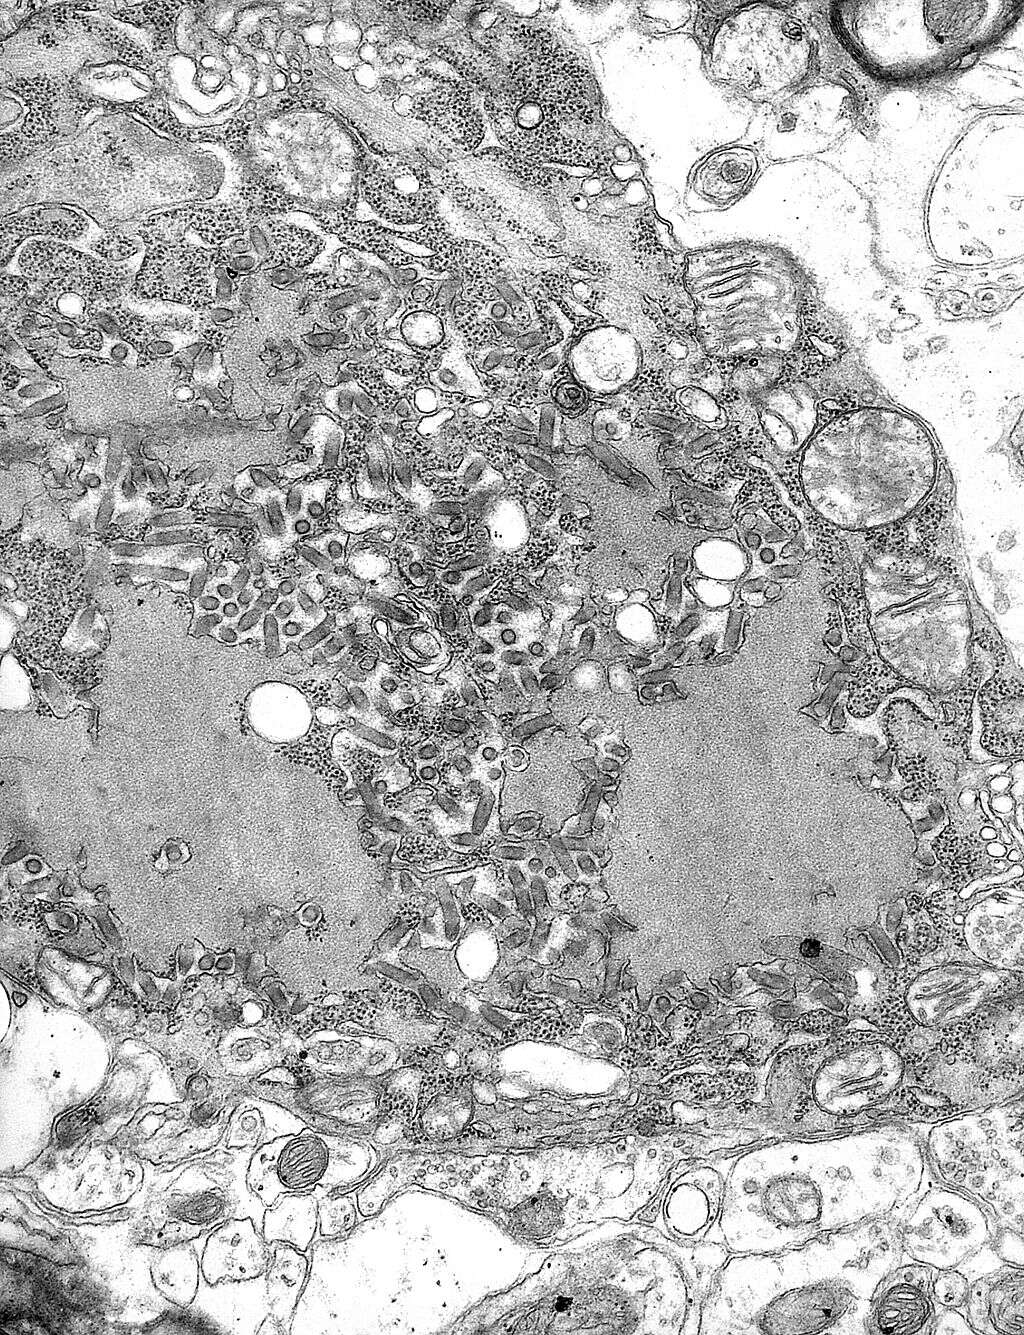

HIV

We współczesnym świecie najbardziej śmiercionośnym wirusem może być HIV. Szacuje się, że od momentu jego rozpoznania na początku lat 80. ubiegłego wieku, na całym świecie z powodu HIV zmarło 36 mln ludzi. Dzisiaj zaawansowane leki przeciwwirusowe umożliwiają wielu osobom żyć z chorobą, ale HIV nadal dziesiątkuje kraje o niskim i średnim dochodzie, gdzie ma miejsce do 95% nowych zarażeń. Według WHO, 1 na 20 dorosłych osób w Afryce Subsaharyjskiej jest nosicielem wirusa HIV.